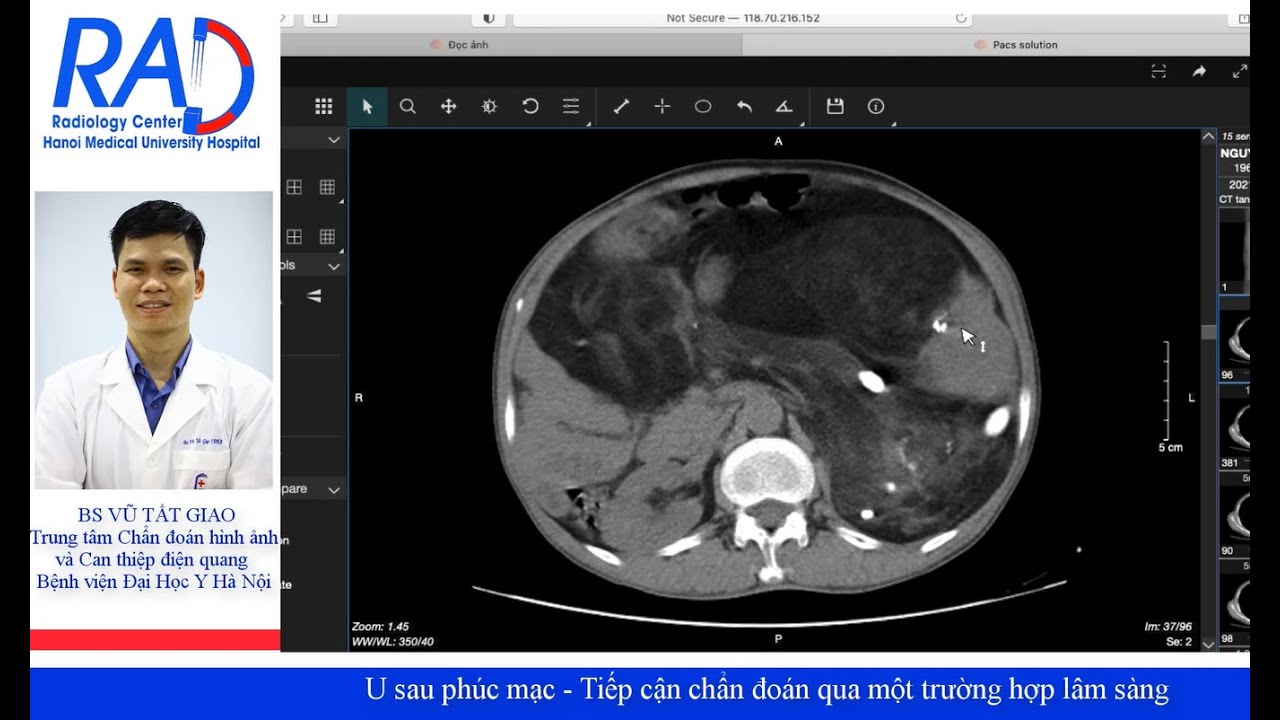

U sau phúc mạc - Tiếp cận chẩn đoán qua một trường hợp lâm sàng

Thực hiện: BS Vũ Tất Giao - Trung tâm Chẩn đoán hình ảnh và Can thiệp điện quang - BV Đại Học Y Hà Nội

Bệnh lý khoang sau phúc mạc khá phức tạp trong chẩn đoán. Các mặt bệnh bao gồm chấn thương, viêm và bệnh lý u. Bệnh lý sau phúc mạc gặp ở: thận, thượng thận, tụy, bàng quang, tuyến tiền liệt, tử cung - buồng trứng, hệ thống bạch huyết, mô liên kết.

Trong ca lâm sàng hôm nay chúng ta cùng phân tích một tổn thương u lớn khá hiếm gặp, qua đó ôn lại cách tiếp cận tổn thương khoang sau phúc mạc.